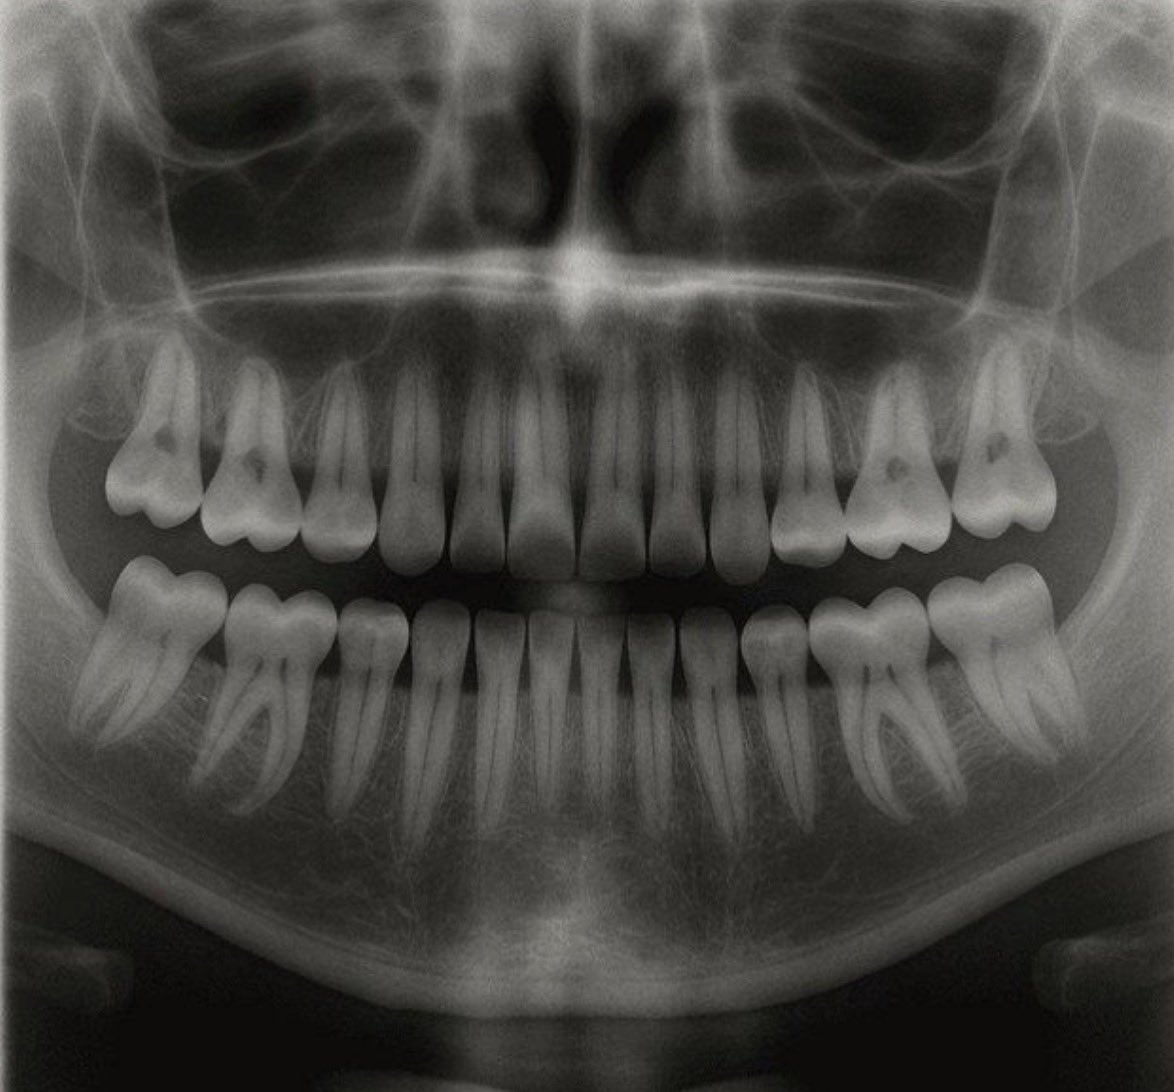

【世界初】日本発の「歯が生える薬」、ついに人間への治験が開始へ 日本の研究チームが、第3の歯を再生させる革新的な薬を開発中です。 2024年秋から臨床試験がスタートしており、2030年の実用化を目指しています。 • 仕組み: 歯の成長を止めるタンパク質の働きをブロック • 対象: 先天性無歯症の方から、将来的には歯を失ったすべての人へ • 展望: インプラントや入れ歯に代わる「第3の選択肢」へ 「失った歯は二度と生えない」という常識が、数年後には過去のものになるかもしれません。